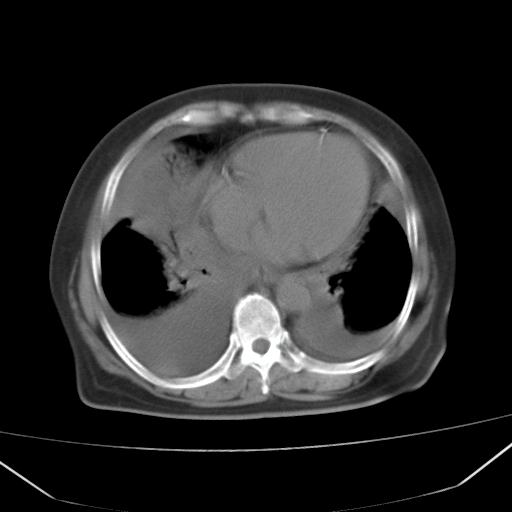

以下是引用liuyue在2008-4-19 22:25:00的发言:[br]先考虑:1.心衰伴肺水肿、双侧胸腔积液、叶间积液、双下肺不完全性肺不张; [br] 2.冠状动脉粥样硬化。

以下是引用lijuanln在2008-4-19 23:05:00的发言:[br]两侧胸腔积液,肺水肿[br]心包积液[br]提示心衰

以下是引用jiangjing在2008-4-20 10:43:00的发言:[br]结合病史支持 冠心病[冠状动脉钙化],心功能不全,肺淤血、肺水肿,双侧胸腔与斜裂积液